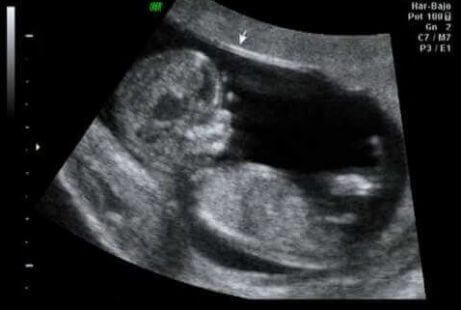

Som et vendepunkt i første trimester kan den 12. uken være et ideelt tidspunkt for den første ultralyden. På denne måten kan vi bekrefte at organene utvikler seg riktig. Vi kan også sjekke babyens størrelse og vekt, samt tilstedeværelsen av nakketranslusens, væsken alle fostre har i nakken.

“Dette er en avgjørende tid, gitt at spesialister hevder at mellom 60 og 70% av misdannelser som fosteret kan presentere, allerede kan oppdages på dette tidspunktet.”

På den annen side måles bredden på fosterets nakkefold, noe som er en del av den første trimester-kontrollen, og som gjør at vi kan oppdage risikoen for en anomali i antall kromosomer (kjent som aneuploidi), spesielt trisomi 21 eller Downs syndrom. Dette er mulig takket være forholdet mellom disse dataene og andre undersøkelser, inkludert:

- Morens alder

- Hormonelle verdier

- Nakketranslusensverdier

Den spennende delen, bortsett fra å legge merke til fosterets første aktivitet, er beregningen av termindato for fødsel. I alle fall, og uten noen hensikt om å legge noen demper på forventningene dine, er datoen bare helt nøyaktig i 5% av tilfellene.